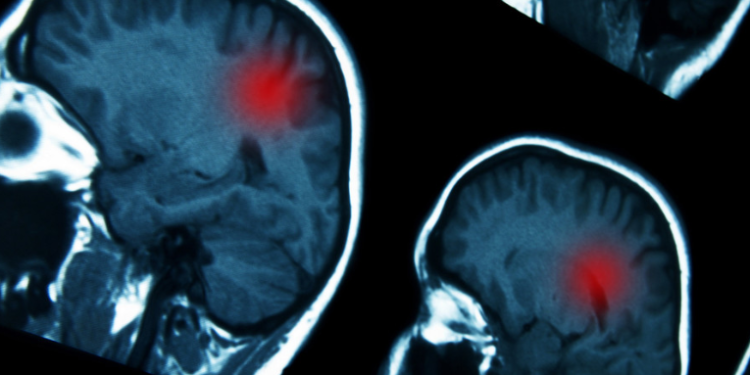

El uso prolongado de ciertos progestágenos, fármacos hormonales que se usan para tratar trastornos ginecológicos, se asocia a un mayor riesgo de desarrollar un tipo de tumor cerebral conocido como meningioma intracraneal, según un estudio publicado este miércoles en la revista médica The BMJ.

Para llevar a cabo la investigación, los científicos utilizaron información del sistema nacional de datos de salud francés de 18.061 mujeres con una edad media de 58 años que se sometieron a cirugía de meningioma intracraneal entre 2009 y 2018.

Así, se concluyó que el uso prolongado (un año o más) de medrogestona se asoció a un riesgo 4,1 veces mayor de padecer meningioma intracraneal que requiriera cirugía, mientras que el uso prolongado de acetato de medroxiprogesterona inyectable se asoció a un riesgo 5,6 veces más alto, y el uso prolongado de promegestona se relacionó con un riesgo 2,7 veces mayor. Sin embargo, no parece existir tal amenaza si estos progestágenos se utilizan por menos de un año.

Los investigadores señalaron que su estudio es el primero que evalúa el peligro asociado con los progestágenos utilizados por millones de mujeres en todo el mundo, y que se necesitan de manera urgente más estudios para comprender mejor este riesgo.